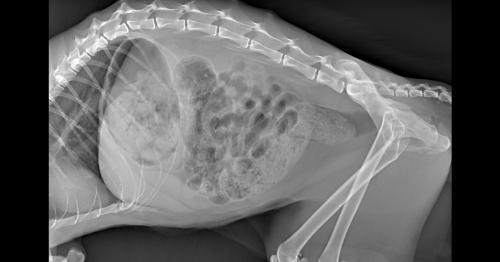

Guarigione completa a 120 gg e rimozione impianto. La casistica riscontrata in medicina veterinaria è molto alta e dovuta soprattutto a gravi traumi ed a malattie dello stesso osso della coscia.

Frattura di femore che si ricompone con mezzo di fissità interno.

Biondi, dvm 1 1 ospedale veterinario gregorio vii, roma, italia. La frattura al femore può essere: .non conoscendo il mondo dei veterinari non so se una pratica diffusa operate una frattura con un fissatore esterno.poi anche le dimensioni di un femore di un gatto sono molto piccole.magari con un fissatore pediatrico o uno per mano. Difficilmente, invece, la zampa viene amputata: Queste fratture sono di solito il risultato di trauma, ma possono essere causate da malattie. Frattura atraumatica dell'epifisi della testa del femore nel gatto. I vostri elaborati > casi clinici. Classificate in base alla sede anatomica. Qual è la terapia più adatta? Il trattamento di una frattura del femore richiede quasi sempre l'intervento di sintesi chirurgica. Frattura comminuta femore distale intercondiloidea. La frattura del femore è un evento particolarmente grave che colpisce in modo schiacciante gli anziani dai 70 anni in su. Quali sono gli esercizi e quando si possono fare? Un'anziana ha riportato la frattura del femore dopo essere caduta questa mattina intorno alle 12 a la donna stava dando da mangiare ad alcuni gatti randagi quando ha perso l'equilibrio ed è caduta. Leggi la voce frattura del femore sul dizionario della salute. Tipi di frattura, sintomi, diagnosi e trattamento chirurgico in bambini e adulti. La frattura del femore si verifica più comunemente in persone giovani e negli anziani.